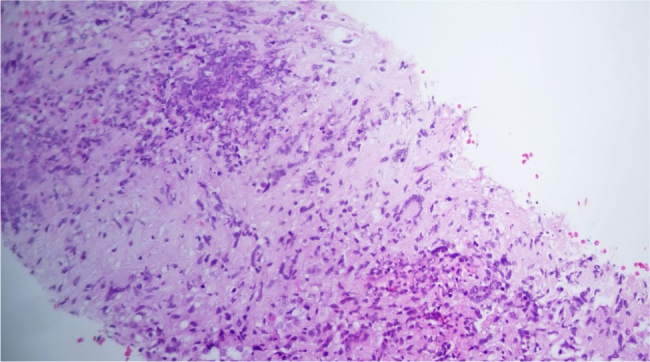

同时出现肺诺卡菌病和肉芽肿病合并多血管炎(GPA)是非常罕见的,并且由于重叠的临床和影像学特征,诊断具有挑战性。我们报告一位54岁女性,有发热、咳嗽、体重减轻和关节痛。胸部影像学示多发肺结节;血清学显示抗中性粒细胞胞浆抗体-蛋白酶3阳性,肺活检显示诺卡菌属坏死性肉芽肿性炎症。这导致肺诺卡菌病和有限型GPA的双重诊断。患者使用复方新诺明后病情有所改善,但由于局限性GPA的表现仍然存在,甲氨蝶呤将在密切监测的同时开始使用。该病例强调了在初步评估疑似血管炎时考虑传染性模拟的重要性,两种实体的双重病理的可能性,以及在控制感染的背景下分阶段治疗此类病例的强调,然后开始免疫抑制治疗。学习要点:肺诺卡菌病在临床和影像学上可能与肉芽肿病合并多血管炎相似,两者很少同时出现。在抗中性粒细胞细胞质抗体阳性患者中,组织病理学检查是区分感染性模拟和血管炎的关键。在开始免疫抑制之前控制感染的分步治疗策略可以降低双重病理并发症的风险。

Concurrent presentation of pulmonary nocardiosis and granulomatosis with polyangiitis (GPA) is exceptionally rare and diagnostically challenging, given the overlapping clinical and radiological features. We report a 54-year-old female with fever, cough, weight loss, and arthralgia. Chest imaging showed multiple pulmonary nodules; serology revealed positive anti-neutrophil cytoplasmic antibodies -proteinase 3, and lung biopsy demonstrated necrotizing granulomatous inflammation with Nocardia species. This led to a dual diagnosis of pulmonary nocardiosis and limited form GPA. The patient improved with co-trimoxazole however methotrexate is set to be initiated concomitantly with close monitoring as the manifestations of limited form GPA were still present. This case highlights the importance of considering infectious mimics during initial evaluation of suspected vasculitis, the possibility of dual pathology of both entities, and the emphasis of the staged approach of treating such cases in the background of controlling infection followed by initiating immunosuppressive therapy.

Learning points: Pulmonary nocardiosis may clinically and radiologically mimic granulomatosis with polyangiitis, and both conditions can rarely present simultaneously.Histopathological examination is crucial to distinguish infectious mimics from vasculitis in anti-neutrophil cytoplasmic antibodies-positive patients.A stepwise treatment strategy in which controlling infection before initiating immunosuppression can reduce the risk of complications in dual pathology.